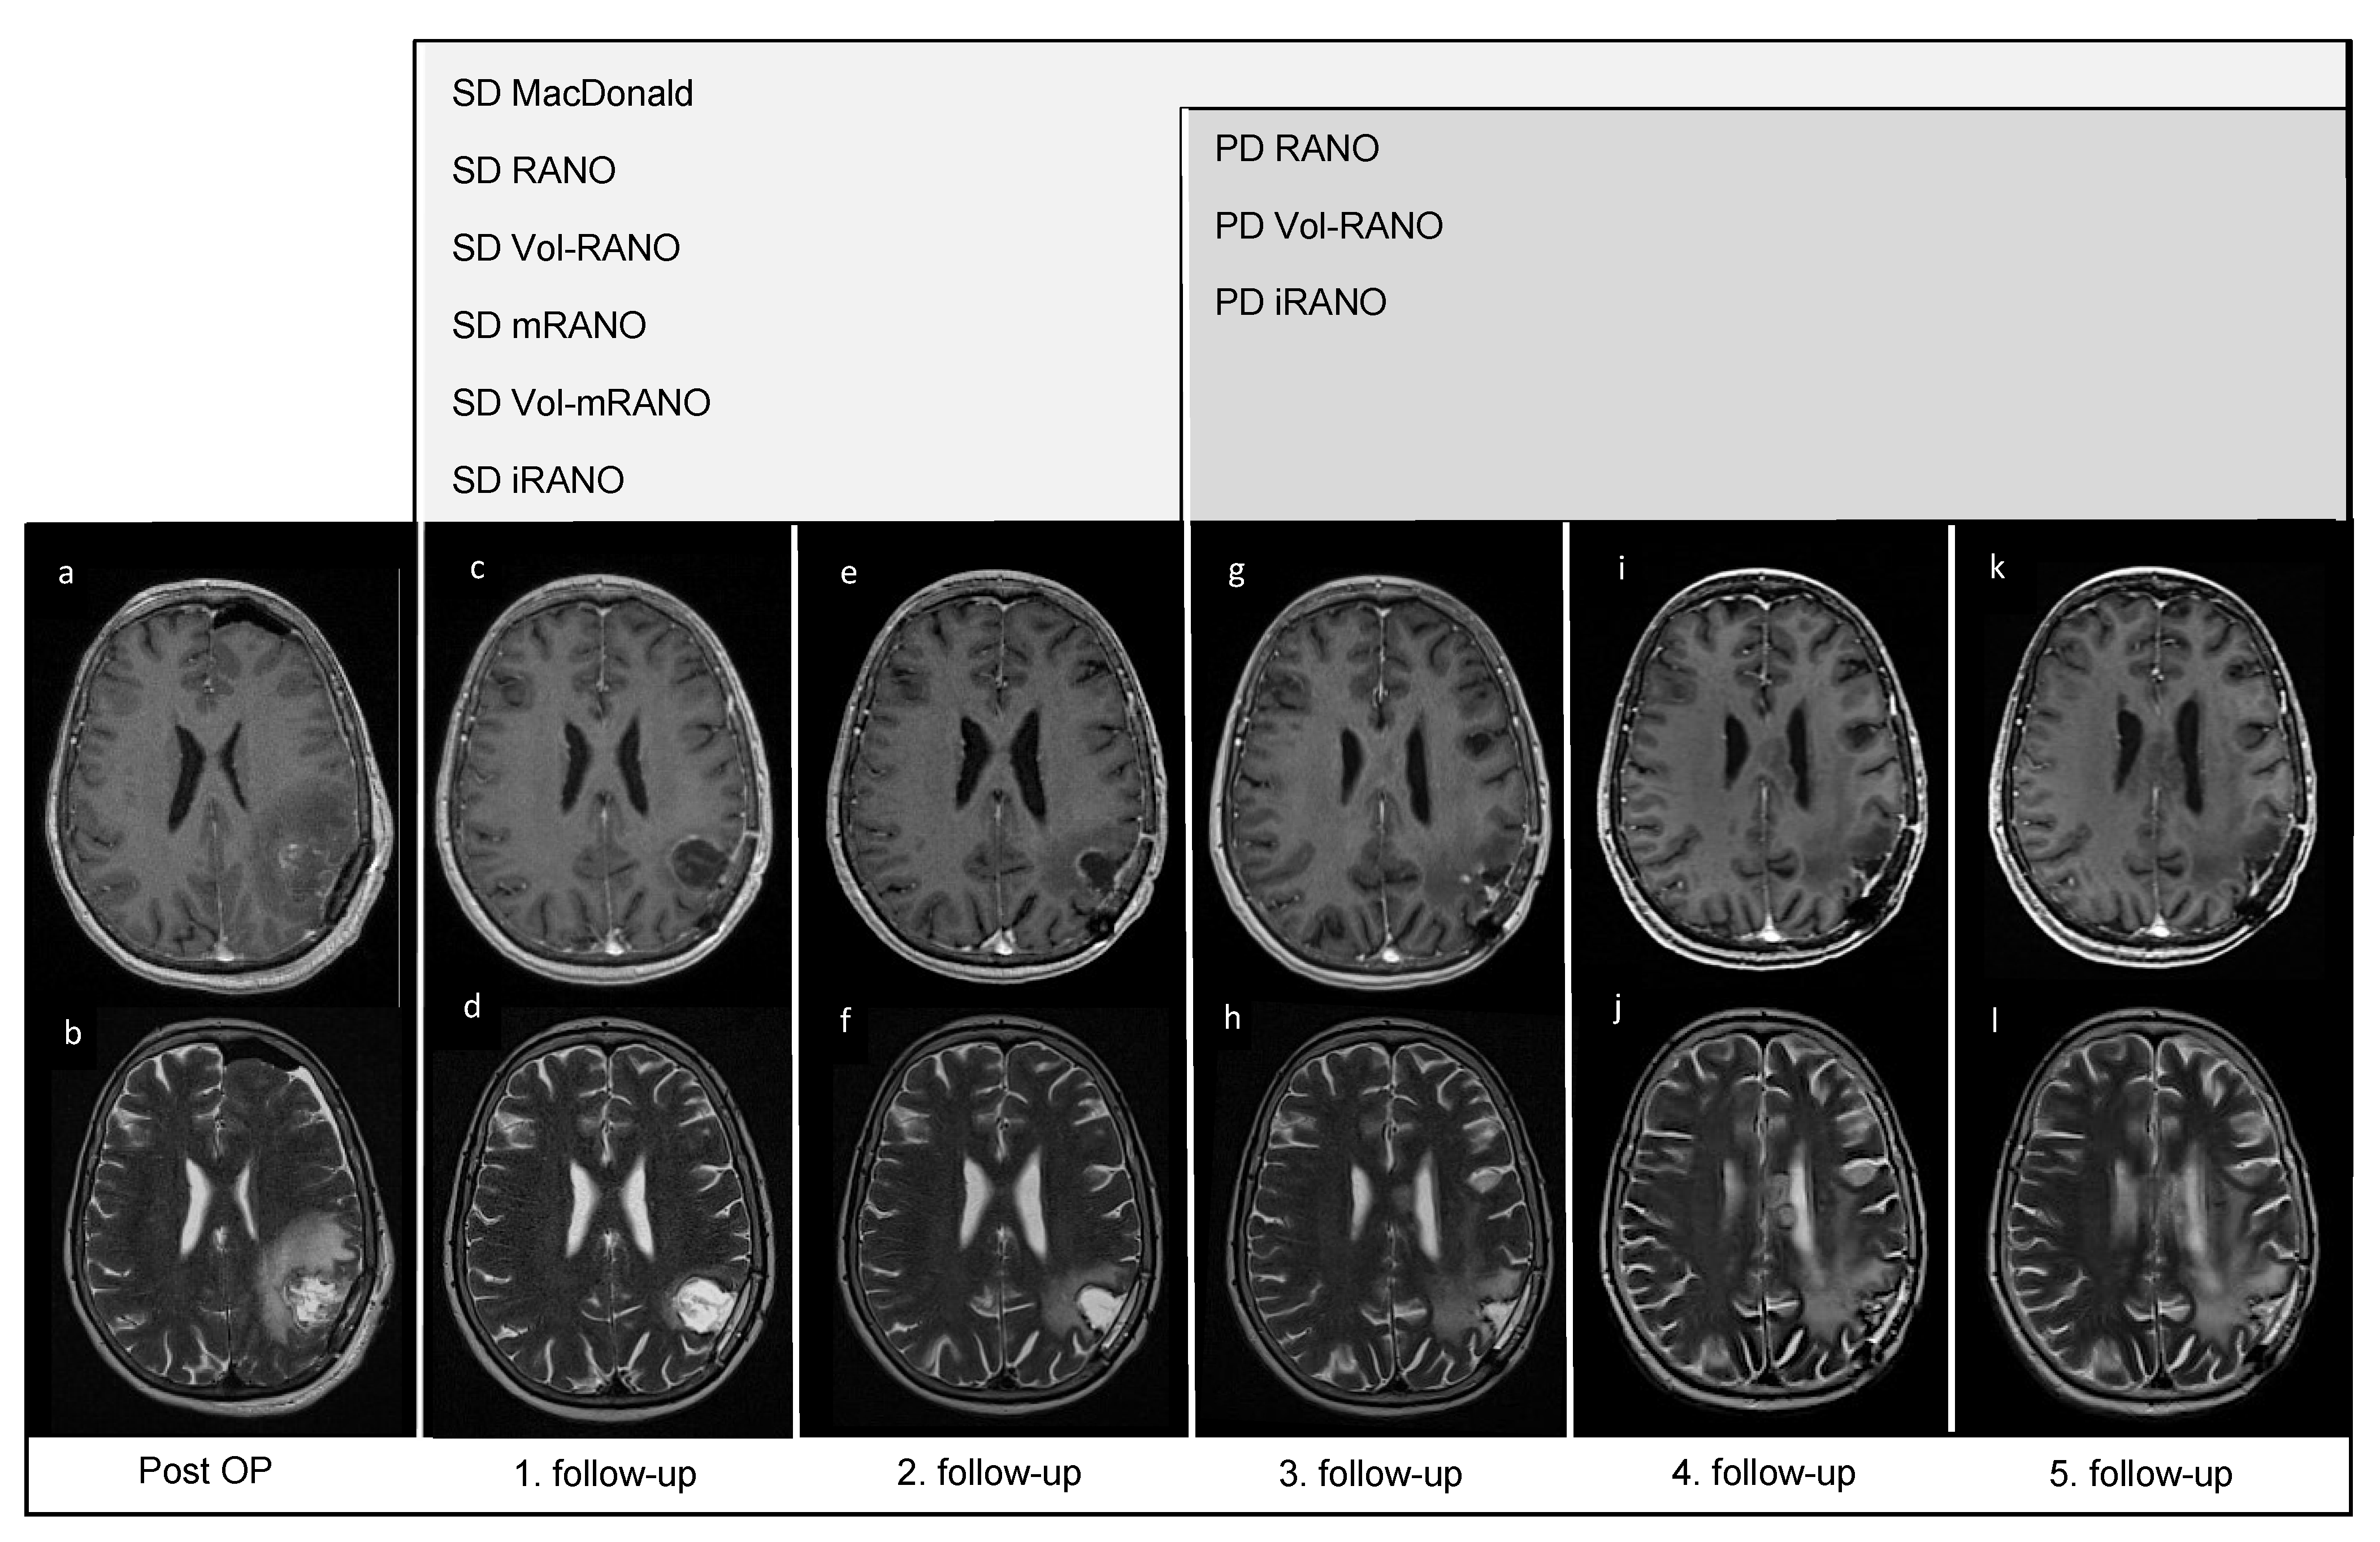

3.6. Pseudoprogression